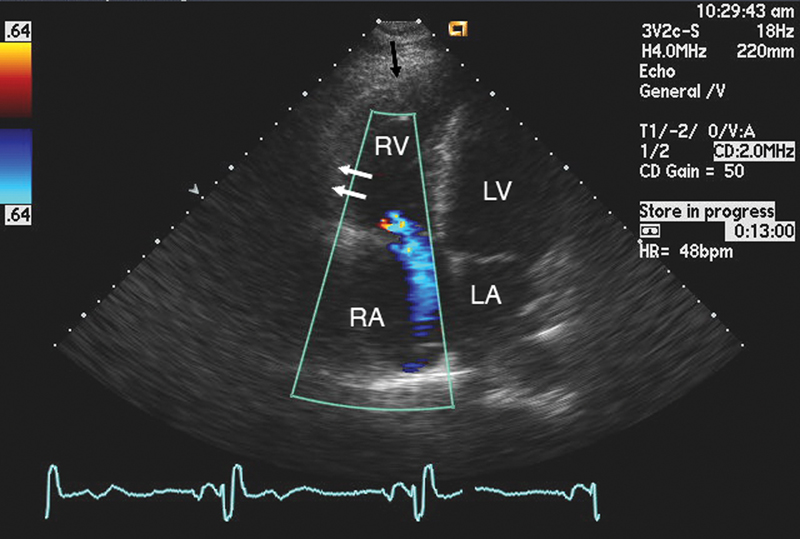

فحوصات تشخيصية لبعض امراض القلب والشرايين التاجية